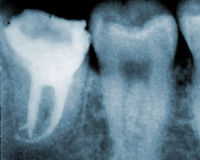

■根管治療

根管治療

むし歯が歯髄まで達し大きく進行している場合や、歯髄炎を起こしている場合、根の管に細菌感染している場合、根の先に炎症が起きている場合など、歯髄(神経)や歯根に問題があるときに行う歯根内部(根管)の治療が根管治療です。

根管治療自体は一般歯科に含まれるものではありますが、その診断から治療テクニックに至るまで、歯科治療全般の中で最も難易度の高い分野の一つになるかと思います。というのも、根管の状態は個々の歯ごとに複雑かつバリエーションが豊富で、しかも深い部分になると拡大鏡(マイクロスコープ)を使っても視認できない範囲が広い上、レントゲン(CT含む)を撮っても限られた情報しか得られず、物理的に器具が届かない部分があったり、細菌の感染範囲は確認できないなどの理由から、根管治療で最終的に物を言うのは、結局のところ歯科医師の手先の感覚や経験と勘からくる主観・想像力によるところが大きいからです。

さらに難しくしているのは治療結果の良否について、長い時間が経ってみないと誰にも言い切れないところでしょう。治療結果は歯を残せるのか、それとも抜歯をしなくてはならないのかの分かれ道になる場合があります。完璧に治療をしたと思っても、数カ月後、数年後に結果はダメだったということが起こりえるのが、この根管治療です。もちろん当院では様々な治療道具やテクニックも駆使して、極力抜かないで歯を温存できるよう、治療結果が最良のものとなるよう確率を高める努力をしています。でもどんな道具や手法であっても、どこまで追求しても確実なものはなく、他の治療に比べると安心が得られにくく難しいと言えます。

根管治療は歯科医師による技量や経験の差が大きく出ることもあり、根管治療を諦めて抜歯に踏み切る判断基準が歯科医師によって分かれてくるところになります。